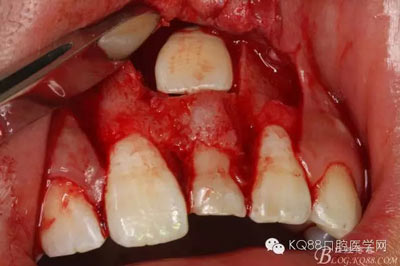

圖11.掀開骨壁。摘除牙瘤及牙囊組織

圖12.摘除囊壁后,暴露出21的切端

圖13.超聲骨刀清理周圍組織,21有Ⅰ°松動